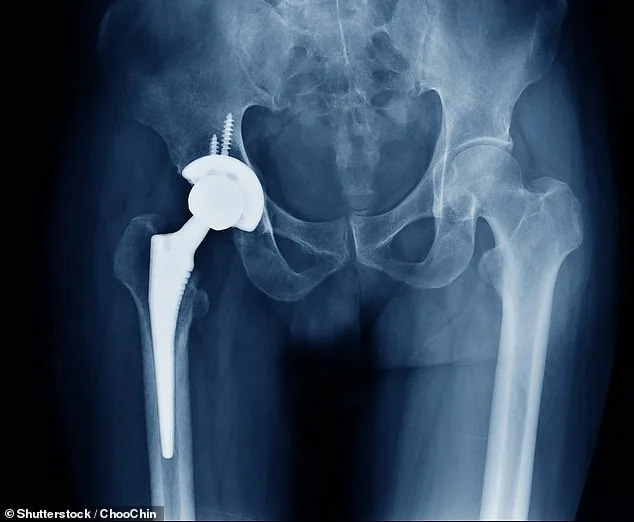

The shortage has left just one week of bone cement supply remaining, a resource used in over 80% of knee replacements and 60% of hip replacements. Each month, around 15,000 procedures rely on this material, which is crucial for securing implants and enabling patients to return to normal life quickly. The absence of cement means surgeries must be postponed or canceled, leaving many with chronic pain and mobility issues. The British Orthopaedic Directors Society and the British Orthopaedic Association have emphasized that emergency trauma cases must take precedence, even as 22,000 patients wait over a year for their procedures.

The crisis has forced NHS trusts to repurpose theatre time for procedures that don't require cement, but this is a temporary measure. Dr. Mark Wilkinson, an orthopedic surgeon, warns that even the best-case scenario—resolving the shortage in two months—will add 10,000 hip and 20,000 knee replacements to existing waiting lists. With only 18% of procedures using alternative cements, the NHS is struggling to meet demand. The situation is dire, with no clear resolution in sight. Patients, healthcare workers, and communities now face a stark choice: endure prolonged suffering or wait for a solution that may take years to develop.